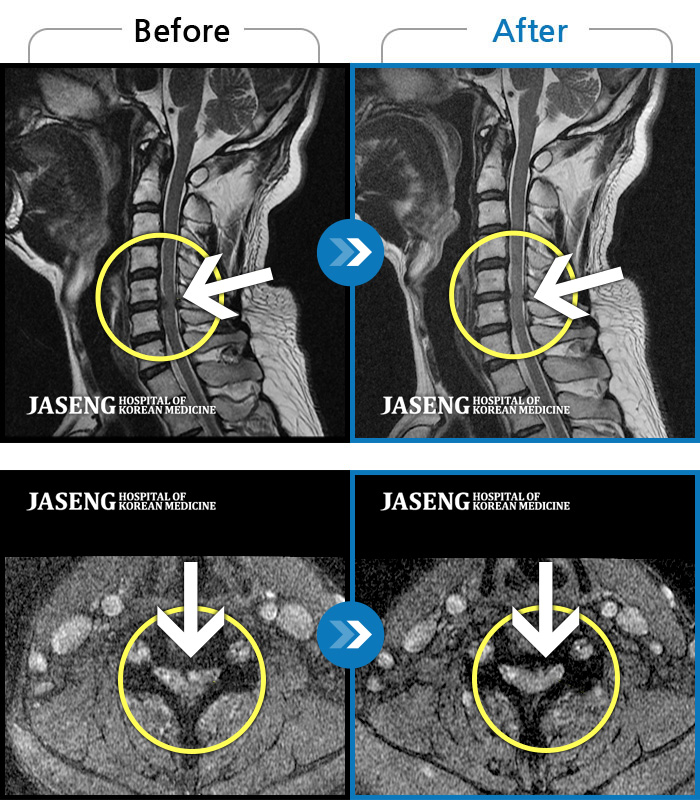

MRI 치료사례

허리디스크

분당 · 진은석 원장

교통사고로 인해 기존의 퇴행성 디스크가 파열되어 극심한 경추의 통증과 손의 힘 빠짐, 손가락의 저림 증상을 호소하였음

촬영시기

2024.04.20 ~ 2024.11.02

2024.11.15